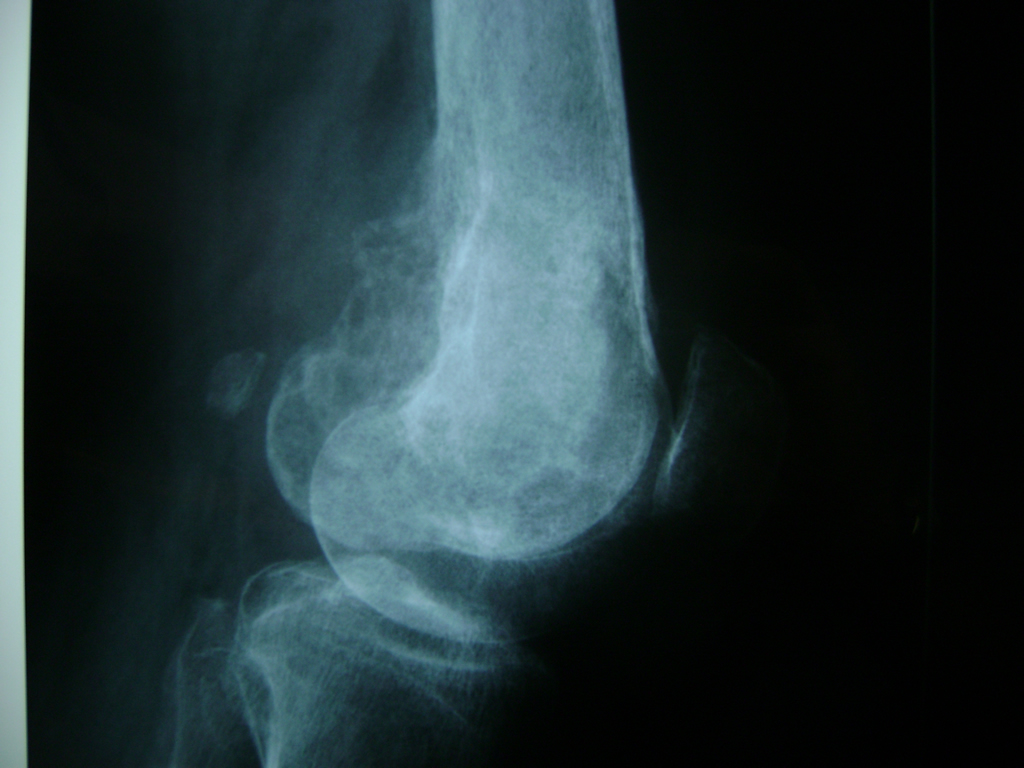

Cirugías de Tobillos

La artroscopia de rodilla es un cirugía en el cual la estructura interna de la articulación es examinada ya sea para realizar un diagnostico o para realizar un tratamiento, este procedimiento se realiza utilizando un instrumento parecido a un pequeño tubo llamado artroscopio.